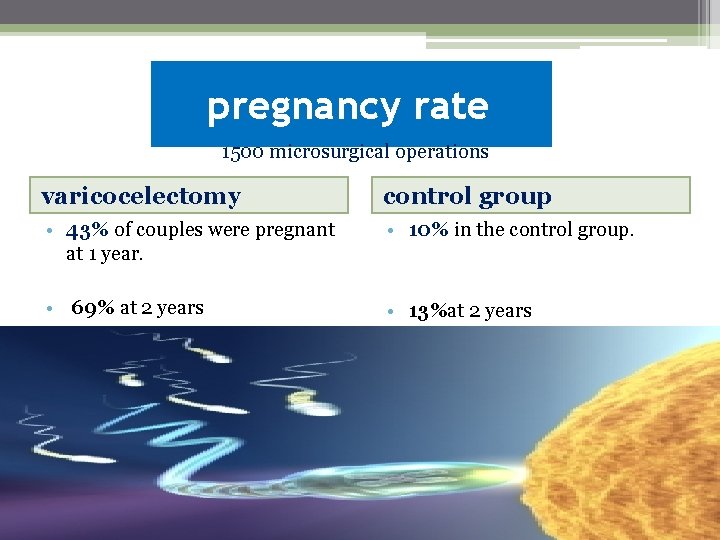

pregnancy rate 1500 microsurgical operations varicocelectomy control group • 43% of couples were pregnant at 1 year. • 10% in the control group. • 69% at 2 years • 13%at 2 years